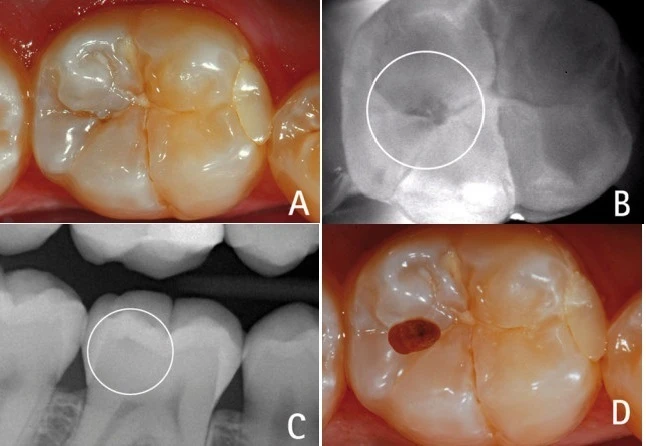

Hình 5: Một lỗ sâu nhỏ trên mặt nhai (A) có thể bị bỏ qua không xử lý nếu chỉ khám bằng mắt thường hoặc với phim X-quang (C). Với sự trợ giúp của Diagnodent có thể thấy sâu răng bên dưới phần men hơi đổi màu (B). Sau khi mở lỗ sâu (D).